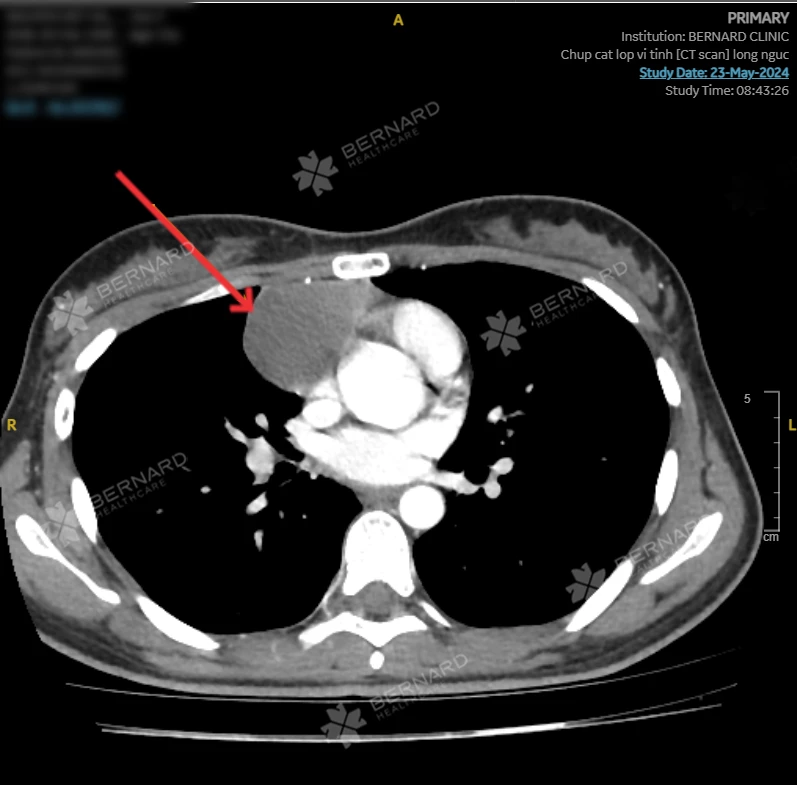

Bằng chuyên môn và kinh nghiệm dày dặn của các bác sĩ Bernard, kết hợp với máy móc thiết bị hiện đại, kết quả trên hình ảnh CT scan ngực của chị V.H. ghi nhận: Tổn thương choán chỗ dạng nang dịch ở trung thất giữa phải, cạnh phải tim, kích thước lớn (37x42x45mm), đậm độ dịch, không bắt thuốc tương phản, nghi ngờ nang màng ngoài tim - một bệnh lý rất hiếm gặp với tỷ lệ là 1/100.000.